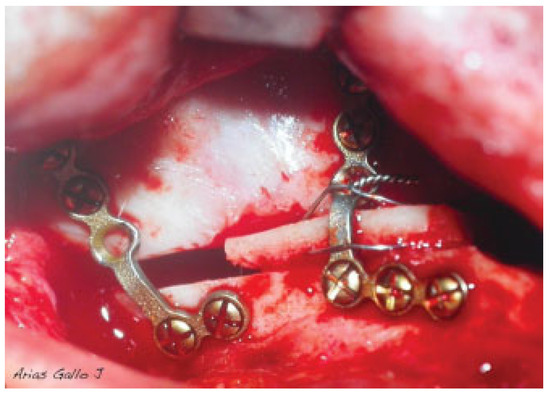

Hereby, we propose a simplified surgical technique with an immediate postoperative positive impact and a promising success rate. Our simplified surgical steps follow. (1) Begin with transposition of the maxillary inferiorly and anteriorly after Le Fort I osteotomy. (2) We emphasize the significance of achieving stable occlusion. (3) Then, we proceed with intermaxillary fixation. The distance of maxilla transportation needs to be planned preoperatively. (4) Next is rigid internal fixation of the dentoalveolar fragment using a customized titanium plate preoperatively. (5) With a tungsten bur, the nasal surface of the maxillary is regularized. (6) Bone grafting blocks are then placed within the gap created by the osteotomy in obtaining the planned vertical height. (7) The bone grafting blocks are fixed in place using a wire that goes beyond the graft and anchors to the custom-made plates (Figure 1 and Figure 2). (8) Finally, check on the maxilla in its new position and new occlusion (Figure 3 and Figure 4). The wire fixation of the grafts allows us to simplify the surgical step of the maxillary repositioning in addition to ensuring the stability of the bone grafts.

Figure 1.

Fixation of the bone blocks with a wire that goes beyond the graft and anchors the plates.

Figure 2.

Sketch of fixation of the bone blocks with a wire that goes beyond the graft and anchors the plates.